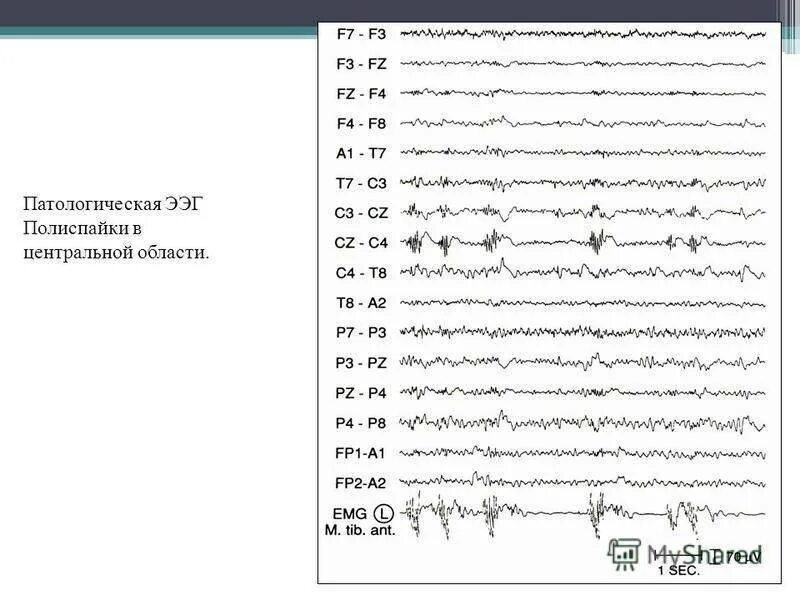

Ээг ребенку зачем